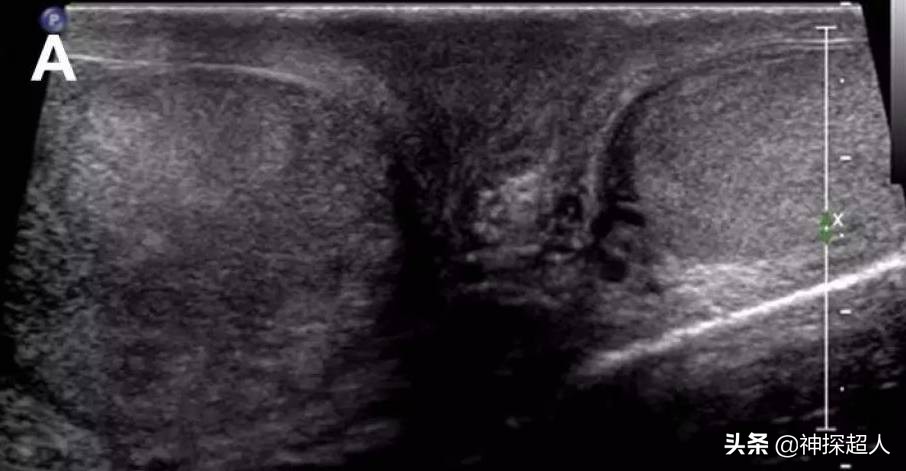

正常*丸睾**彩超声像图

右侧*丸睾**扭转声像图

彩色多普勒超声: 为诊断*丸睾**扭转的首选检查方法,准确率接近90%。超声检查可显示*丸睾**血流信号减弱或消失,还可以帮助区分扭转与附睾炎。*丸睾**扭转者在早期,超声下可见*丸睾**回声轻度肿大,彩色血流信号减少。扭转继续或加重,则*丸睾**明显增大,彩色血流信号明显减少或消失,*丸睾**周围出现少量液性回声,阴囊壁软组织增厚。晚期病例,*丸睾**坏死内部回声不均匀,周围液性回声增多,彩色血流信号消失。